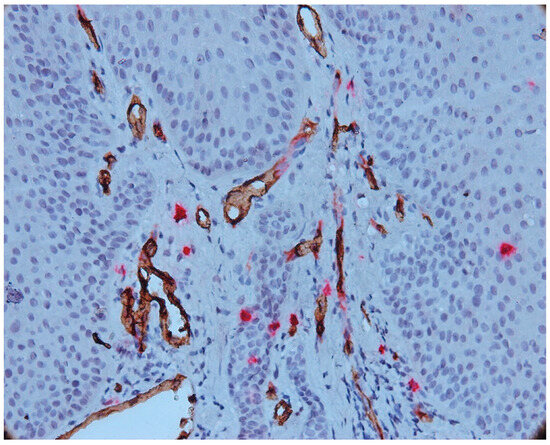

3.2. Mast Cells

3.3. Aspects of Microvessels

3.4. MCD and MVD